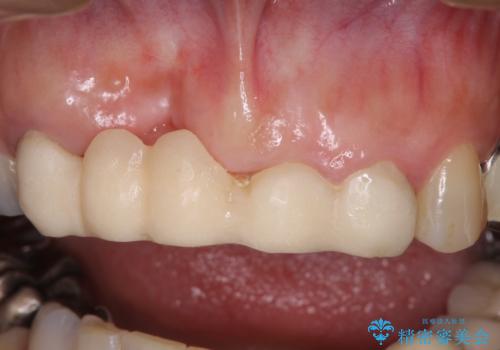

- 前歯のブリッジ治療中に装着していた仮歯が、あまりにも不自然で気になるとのことで来院された患者様です。

早急に仮歯をきれいなものに付け替え、オールセラミックブリッジにより補綴することとしました。